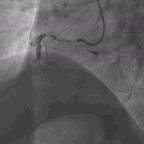

接下来的问题是结束手术,还是锦上添花处理回旋支或继续处理前降支中段?因前降支中段涉及很大的对角支,如果在前降支中段植入支架势必会影响对角支血流,既然前降支血流明显改善,冒此风险不值得,故未在前降支中段植入支架。最终我们决定一不做二不休处理回旋支,考虑回旋支OM2最大,但有慢性闭塞病变,处理起来不容易,遂决定处理回旋支远端,将Rinato导丝送至回旋支远段,用小球囊Ryujin(1.5*8)扩张(图7)后血流改善(图8),最终结束手术。

图7. 小球囊Ryujin(1.5*8)扩张

图8. 最终结果